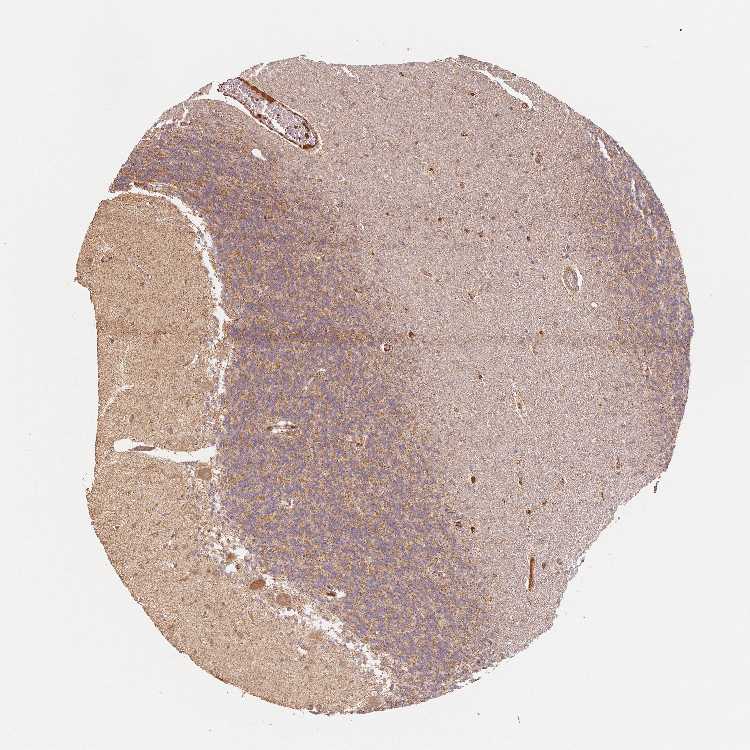

CEREBELLUM - Antibody stainingi

Antibody staining in the annotated cell types in the current human tissue is reported as not detected, low, medium, or high, based on conventional immunohistochemistry profiling in selected tissues. This score is based on the combination of the staining intensity and fraction of stained cells.

Each image is clickable and will lead to virtual microscopy that enables deeper exploration of all samples and also displays staining intensity scores, fraction scores and subcellular localization as well as patient and tissue information for each sample.

Antibody HPA065016

Purkinje cells Medium

Cells in granular layer Medium

Cells in molecular layer Low